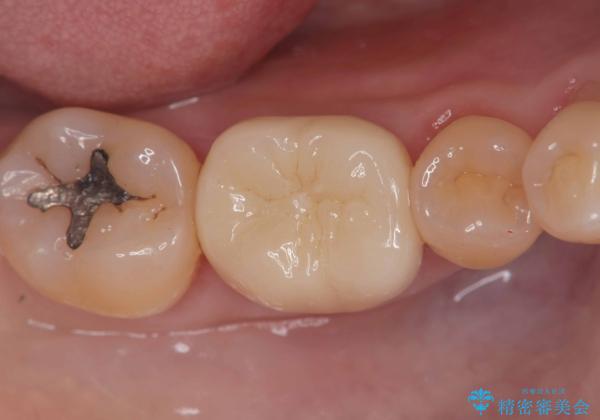

- 「銀歯を白くしたい」を主訴に来院された患者様です。銀歯を外し虫歯を除去後、オールセラミッククラウンで治療を行いました。

銀歯を外して内部の虫歯を丁寧に除去した後、オールセラミッククラウンにて修復を行いました。審美性と機能性の両面で改善が得られ、患者様にもご満足いただきました。